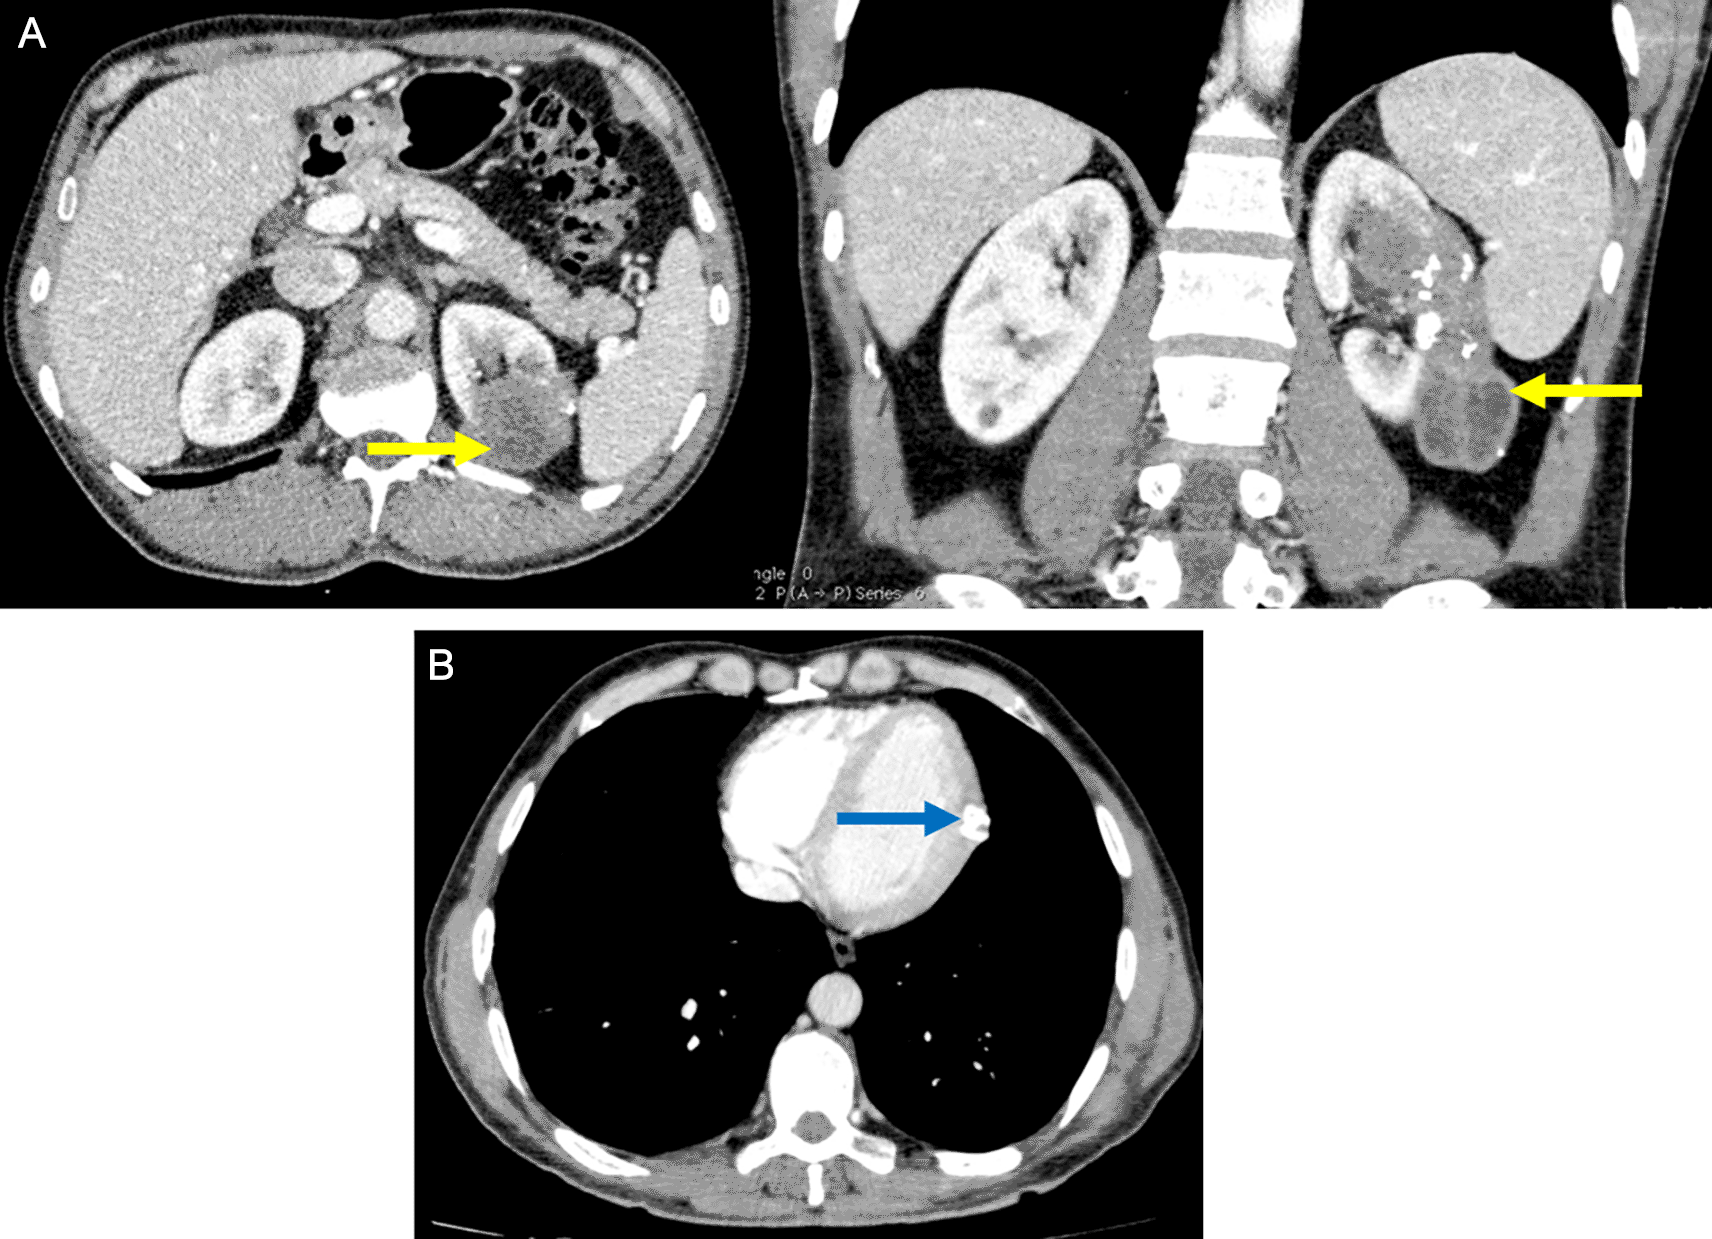

The patient was followed up at the department of abdominal surgery for a multiple organ hydatidosis including 13 hydatid cysts: the lungs, the liver ( Figure 1), the left heart ventricle, the left kidney (Figure 2), the abdomen cavity, the muscles (psoas, adductors), and the subcutaneous gluteal area. The majority of these cysts were already treated surgically and some of them are scheduled to be removed (Table 1). The patient has received oral Albendazole 400 mg twice-daily for 2 years.

Renal involvement is also rare (2–3%) and it is usually associated with disseminated disease, they are most commonly asymptomatic, as reported in the present case. The diagnosis was made by an abdominal CT scan which has a sensitivity of 98% in diagnosing hydatid disease.7

Psoas cysts are also uncommon.8 The patient presented with two psoas cysts, a finding that has never been reported in the literature.

The patient has also presented with a 30-mm gluteal subcutaneous cyst, this involvement was described in rare cases in the literature. Patients usually have a painless palpable mass of at least 3 months, and it is usually larger than 3 cm, as it is reported in the present case.9 Subcutaneous cysts tend to involve the trunk and the limb roots, possibly due to the rich vascularization and the relatively lower activity of the muscle in these areas.10